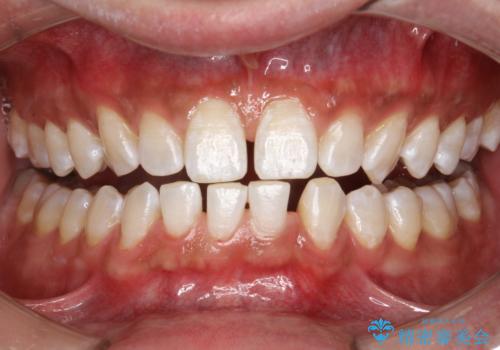

- ホワイトニングで、できる限り白くしたいとのことで来院されました。処置前クリーニング(¥3,300)・エクセレントホワイトニング(¥29,700)・トリートメント(¥550)を行いました。